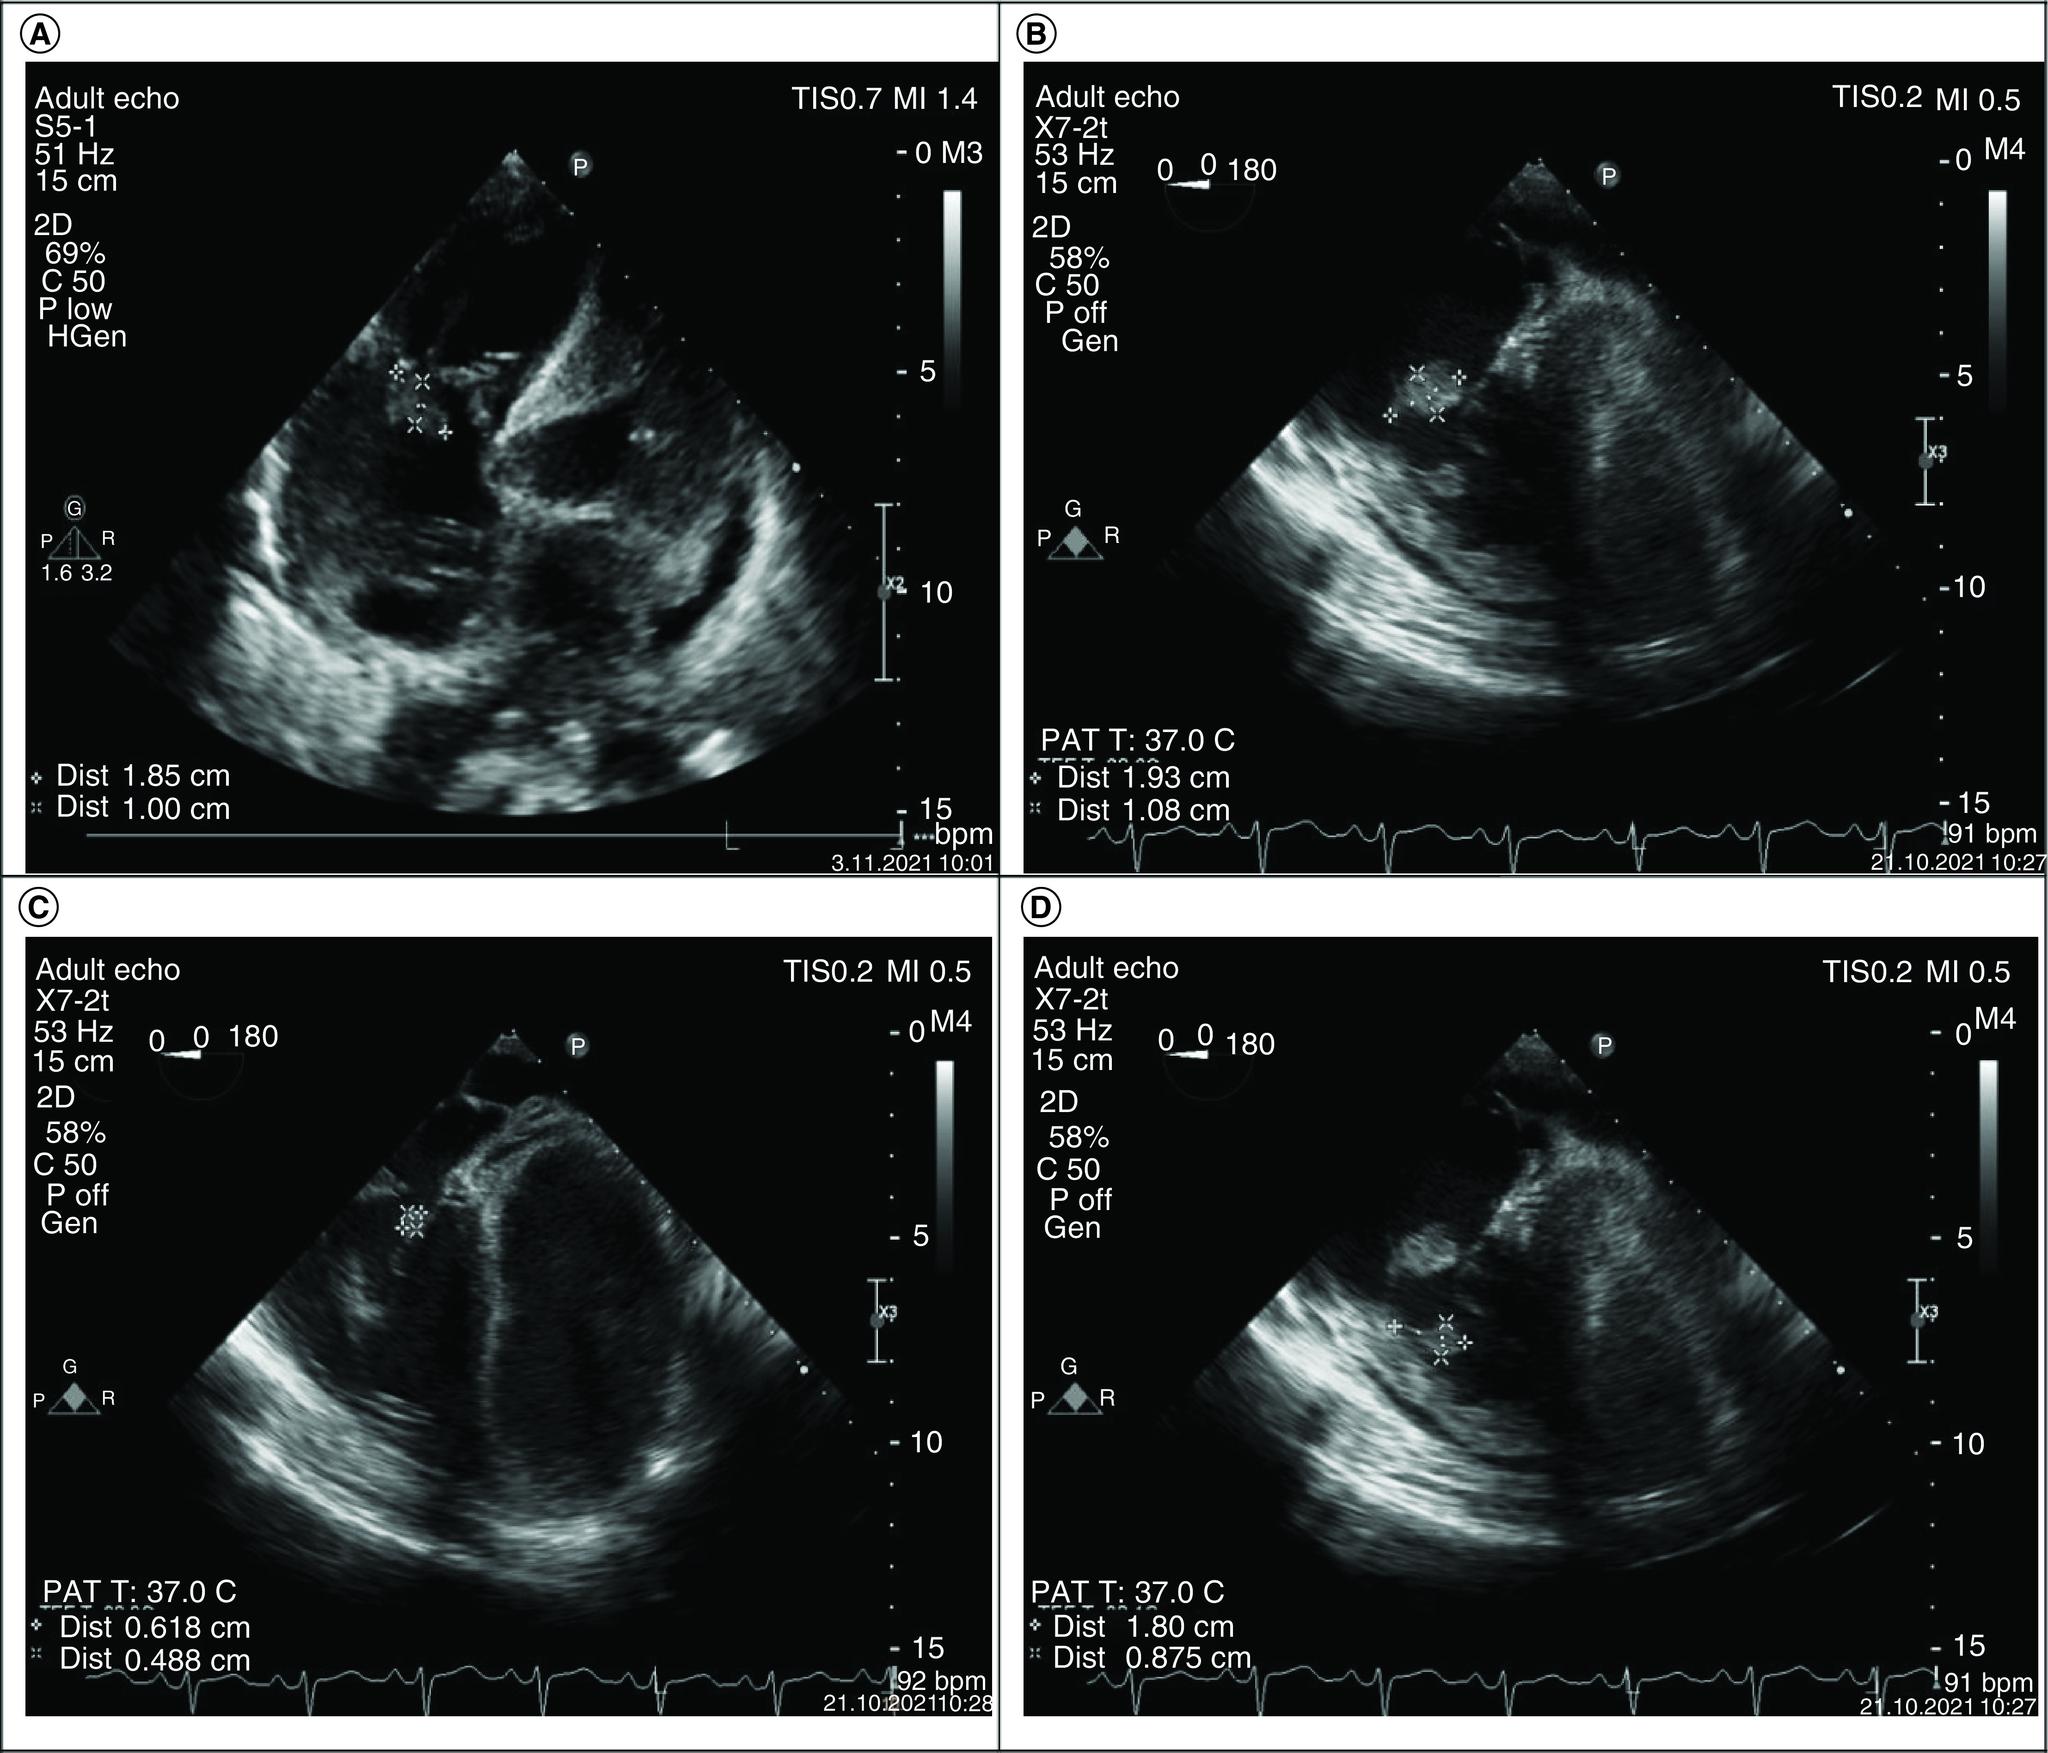

A rare case of septic pulmonary embolism in co-existence with infective endocarditis and COVID-19.

Infective endocarditis (IE) symptoms including fever, fatigue, dyspnea and myalgia are similar in COVID-19 findings. Therefore, the diagnosis of IE may be missed in patients with COVID-19. Co-existence with IE in COVID-19 is rarely reported. However, to our knowledge, only one case of septic pulmonary embolism in COVID-19 and IE was reported. Here, we describe a case of septic embolism due to tricuspid endocarditis caused by intravenous drug use in patients with COVID-19. In this fatal case, the use of prophylactic anticoagulants due to COVID-19 probably caused the tendency to hemorrhagic cerebrovascular complications. Our report emphasizes the complexity of anticoagulant prophylaxis in patients with COVID-19 which may cause hypercoagulopathy in co-existence with IE.